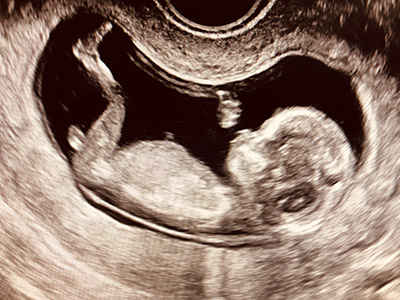

Kinderwunsch - warum klappt es bei uns nicht?

"Ich habe Angst, da ich bereits mehrere Fehlgeburten hatte!" "Wir planen eine Schwangerschaft, was müssen wir bedenken?"

Wir versuchen mit Ihnen gemeinsam Antworten auf diese Fragen zu finden. Mit einer Hormonanalyse, ggf. einem Zyklusmonitoring und einer ausführlichen Beratung werden wir die diagnostischen und therapeutischen Möglichkeiten besprechen.